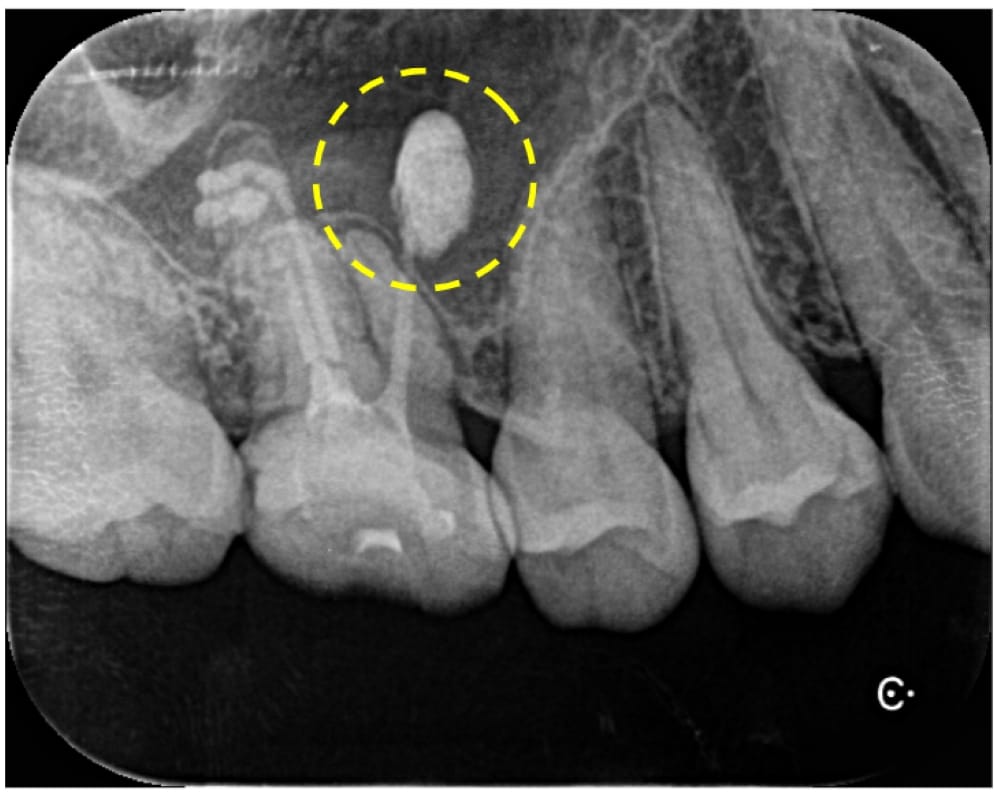

右上6番は、近心根管のパーフォレーション(穿孔)が疑われ、そこから根尖孔外へレントゲン的に白く写る不透過性物質の押し出しが確認できました。性状から、貼薬材料あるいは根管充填に使用するシーラーであると推測されました。

もともとラバーダムなしで根管治療が行われていたことから、根管内の細菌感染が疑われる状態であったため、まずは通常通りの非外科的な根管治療を行い、治癒しない場合に外科的歯内療法へ移行することになりました。